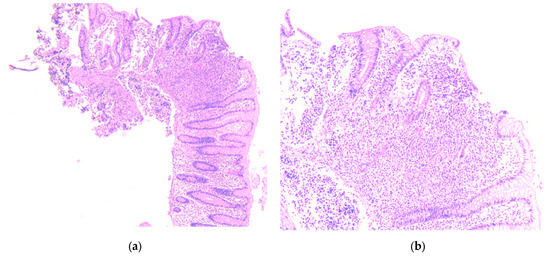

Given the high suspicion of malignancy, the patient has been scheduled for a thoraco-abdominal computed tomography (CT) scan. In the meantime, additional investigations—including esophagogastroduodenoscopy (EGD) and lower gastrointestinal endoscopy (LGE)—were performed to identify the primary source of the liver metastases. EGD showed no significant changes, with a normal gastric stump, while LGE revealed a mucosa with a normal appearance up to the ileocecal valve. A small sessile polyp, measuring 8 mm in diameter, was identified at the level of the cecum and was removed through endoscopic polypectomy. Histopathological analysis of the resected cecal polyp revealed fragments of mucosa infiltrated by a cellular proliferation with a predominantly solid architecture, extending into the submucosa. The tumor cells were monomorphic with scant cytoplasm and hyperchromatic nuclei. Critically, the mitotic rate was high, formally reported as >20 mitoses per 10 high-power fields (HPF) (Figure 2a,b). Immunohistochemical staining was positive for chromogranin (Figure 3a) and synaptophysin (Figure 3b) as well as for B-cell lymphoma 2 protein (BCL-2), and was focally positive for p53. The Ki-67 proliferation index was >30% (Figure 4). These features led to a definitive diagnosis of small cell neuroendocrine carcinoma of the cecum.

Figure 2.

Fragment of cecum mucosa, hematoxylin-eosin staining. (a) 5×—the tumor distorting the normal glandular structure; (b) 10×—the tumor exceeds the muscularis mucosae and invades the submucosa.